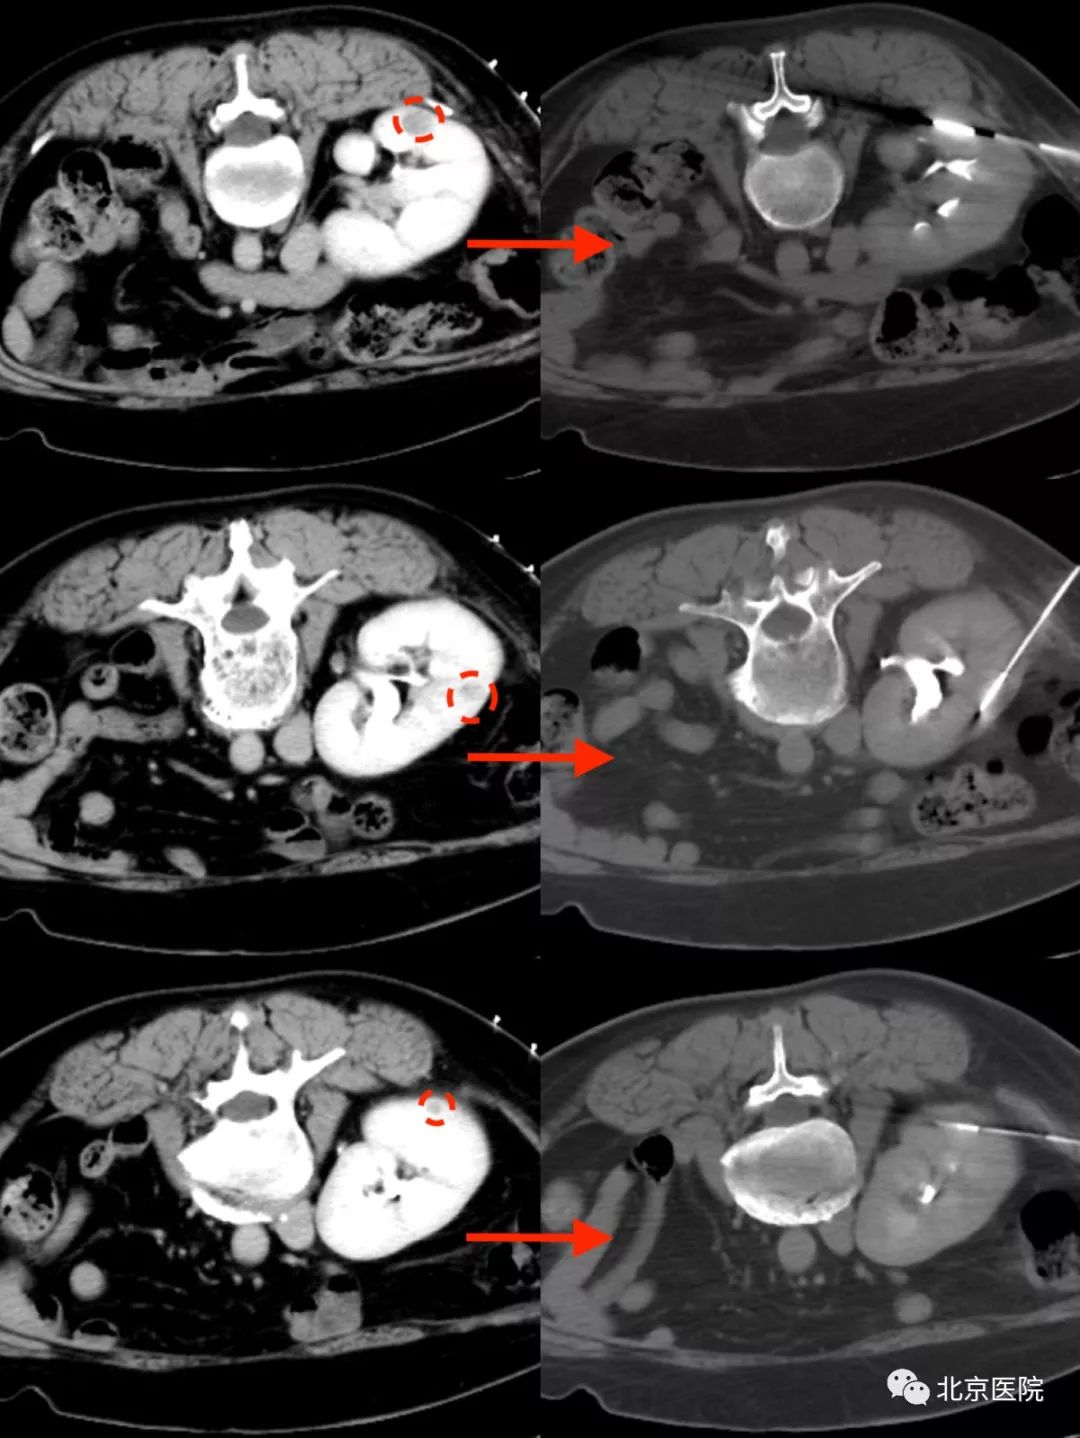

术前增强CT提示三处病灶(左)及术中穿刺定位(右)

近日,北京医院泌尿外科收治了一名中年女性,6年前因双肾同时发现肾癌,接受了左肾癌根治性切除术、右侧保留肾单位的肾部分切除术,术后规律复查,1月前 CT扫描发现右肾内出现可疑的肿瘤复发,进一步行磁共振检查发现3处可疑病灶,全身其他部位未见转移。考虑患者仅有一个不完整的肾,又复发了多个小的肾肿瘤,目前肾功能正常,若行根治性肾切除,则必然需要长期透析治疗,严重影响生活质量;若再次行肾肿瘤部分切除术,因为手术区域粘连,同时仅一处复发灶外凸明显,另两处病灶B超定位困难,手术难度极大,难以保证彻底消灭肿瘤。北京医院肿瘤微创治疗中心李晓光主任团队借助CT引导下精准定位技术,对这三处病灶实施一次性经皮穿刺活检同步微波消融治疗。患者仅需俯卧在CT检查床上保持不动,局部麻醉、只有几个穿刺针眼、不到一个小时就达到了彻底灭活3个肿瘤的目的。整个治疗过程中患者没有不适感觉,与医生自如交流,术后第二天,患者即顺利出院。